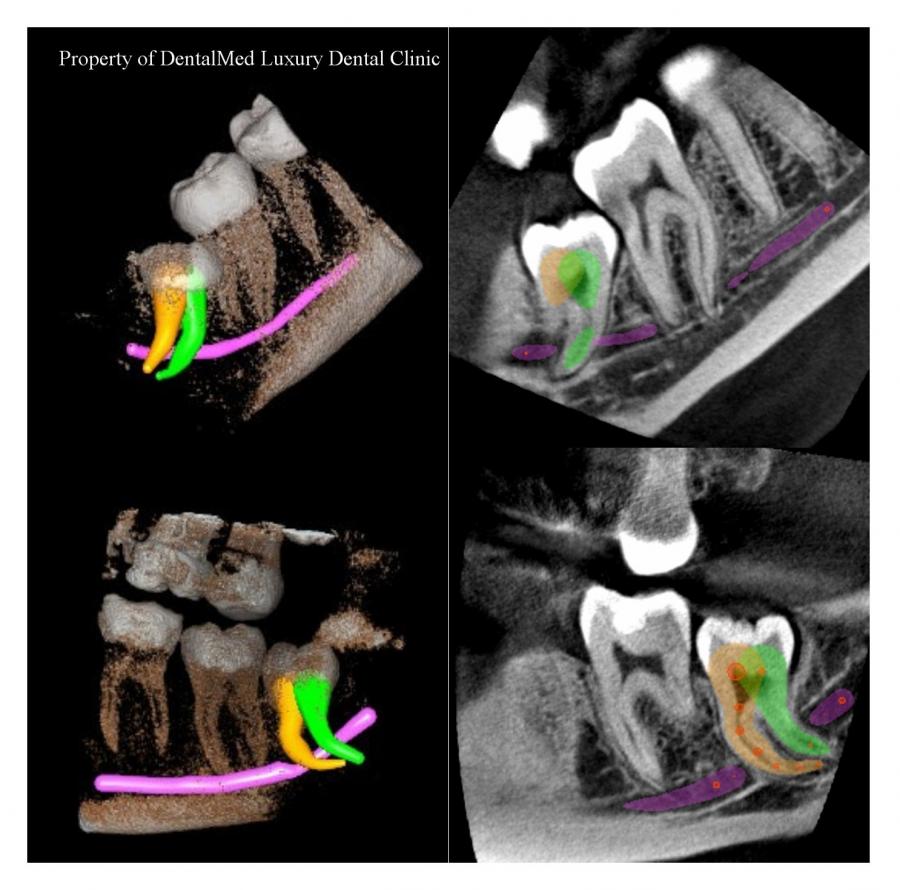

Imagistica dentara